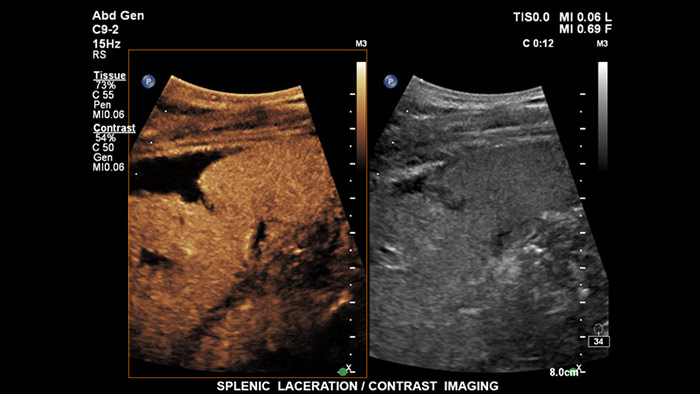

Los agentes de contraste para ultrasonidos pueden transformar el papel que desempeñan los ultrasonidos hepáticos, pues permiten que el usuario estudie los patrones de mejora de las lesiones hepáticas sospechosas en tiempo real, lo que ofrece la posibilidad de realizar diagnósticos más fiables y rápidos. Con EPIQ de Philips, los CEUS se integran a la perfección en el flujo de trabajo normal y proporcionan un nivel de detalle excepcional en exploraciones de la fase arterial, portal y tardía. Además, EPIQ ofrece el mayor nivel de fiabilidad posible para la detección y caracterización de lesiones, incluso en las exploraciones más difíciles; esto es posible gracias a tecnologías avanzadas al alcance de su mano, entre las que cabe mencionar las siguientes: pantalla MaxVue FHD, transductor PureWave C9-2, imágenes de fusión y cuantificación Q-App.

Los agentes de contraste para ultrasonidos pueden transformar el papel que desempeñan los ultrasonidos, pues permiten que los profesionales sanitarios estudien los patrones de mejora de las lesiones hepáticas en tiempo real, lo que ofrece la posibilidad de realizar diagnósticos más definitivos y rápidos. Con los ultrasonidos de Philips, los ultrasonidos con contraste se integran a la perfección en el flujo de trabajo normal y ofrecen un nivel de detalle excepcional.